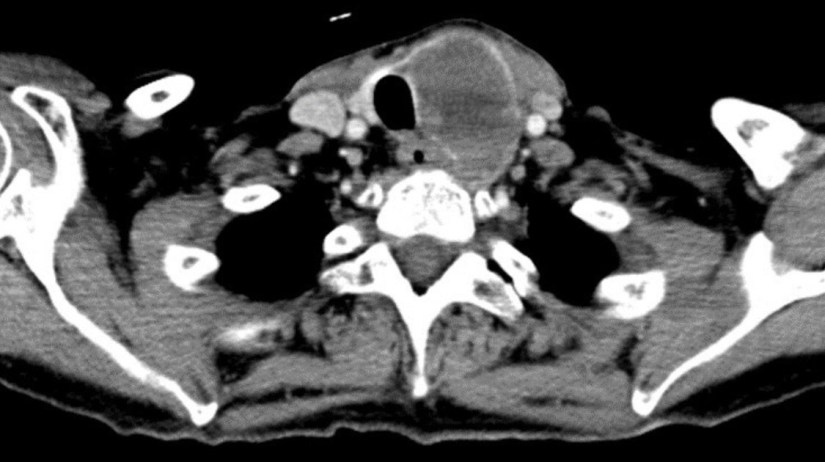

👉Muchos cánceres de tiroides se encuentran por accidente en una tomografía computarizada realizada por otros motivos – Dr. ARRANGOIZ